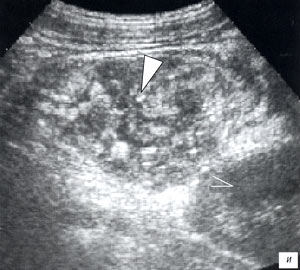

Мезентериальные лимфатические узлы: УЗИ и диагностика

Раздел: Лаборатория идей